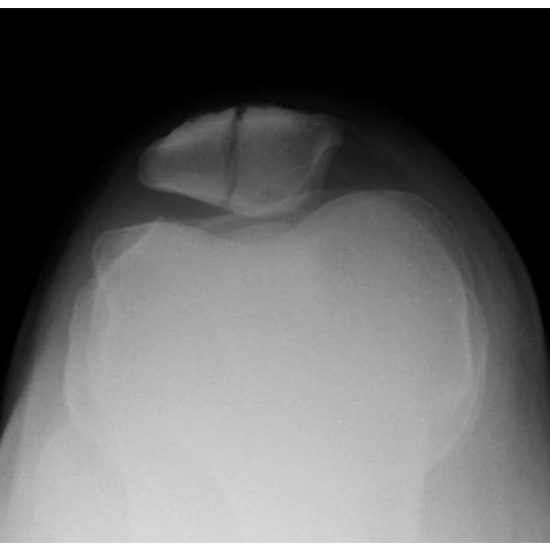

What is an X-ray Both Patella LAT and Skyline Axial Views Test?

X-Ray Both the Patella LAT and Skyline Axial Views assess the ability to visualize the knee cap. There is a triangular bone that covers the knee joint called the patella. The patella is connected to the lower end of the femur (thigh bone).

The doctor will order this test if he or she thinks that the knee cap is broken or out of place (patella).